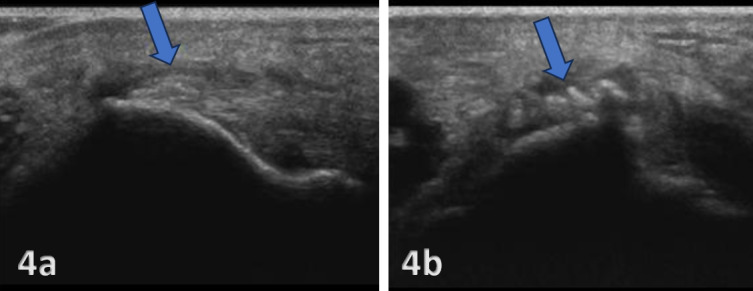

En la imagen A, en eje longitudinal, se observa una tendinopatía crónica del tendón extensor común. El tendón aparece engrosado y se identifican calcificaciones intratendinosas, visibles como pequeños focos hiperecoicos señalados por la flecha azul.

En la imagen B, en eje transversal, se vuelven a observar esas calcificaciones dentro de la masa extensora, señaladas por la flecha azul. Se ven como focos o trazos hiperecoicos, es decir, más brillantes que el tejido tendinoso que las rodea.